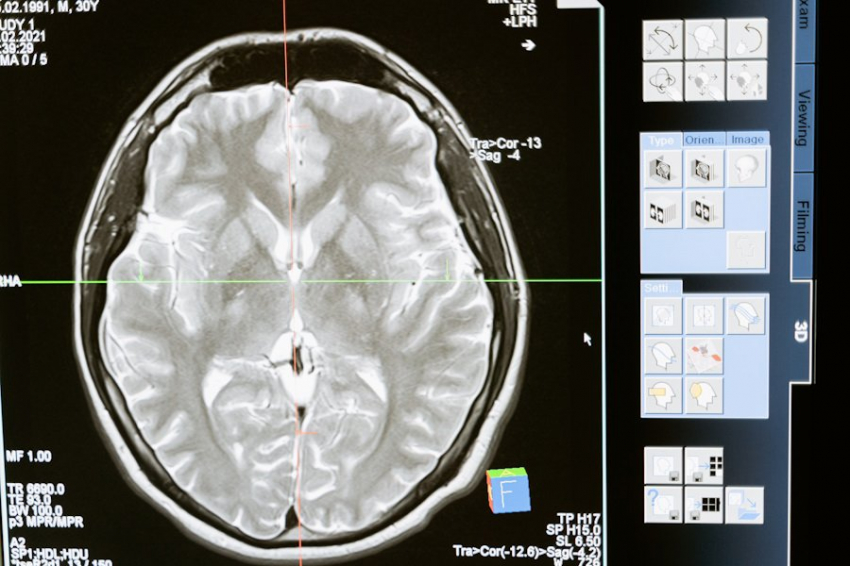

Новое исследование показало, что у людей с шумом в ушах есть повреждения определенных волокон слухового нерва, которые не обнаруживаются стандартными тестами на слух. Кроме того, нейроны ствола мозга — области в нижней части мозга, которая соединяется со спинным мозгом — более активно реагируют на шум у людей с шумом в ушах, чем у тех, кто никогда его не испытывал.

Однако когда авторы поместили электроды в уши участников и измерили электрическую активность слухового нерва и ствола мозга в ответ на щелкающие звуки, они обнаружили, что у людей с шумом в ушах поврежден определенный тип волокон, которые реагируют на более громкие звуки.

Во внутреннем ухе находится камера в форме улитки, которая содержит клетки, которые улавливают вибрации и преобразуют их в электрические сигналы. Эти сигналы затем передаются по волокнам слухового нерва через ствол мозга в слуховую кору головного мозга, которая интерпретирует сигналы как звуки.

В ходе исследования у людей с шумом в ушах также наблюдалась более высокая активность нейронов ствола мозга в ответ на щелкающие звуки. Мейсон считает, что это отражает то, как мозг компенсирует потерю функции слухового нерва.